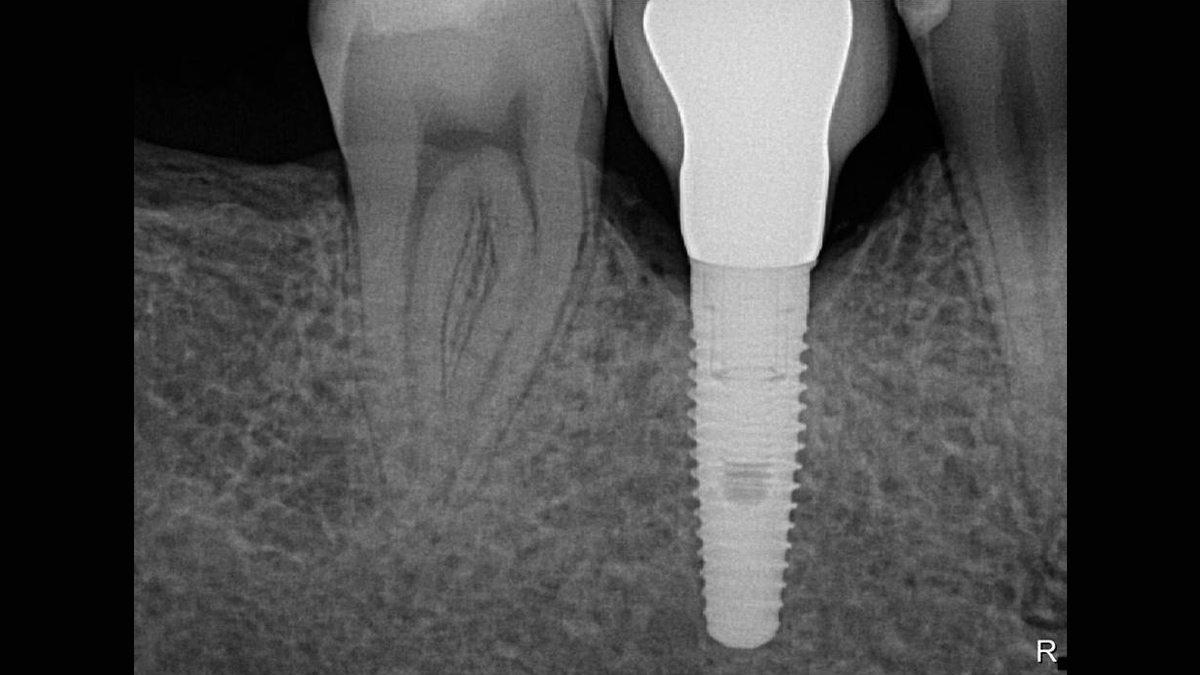

Los sensores intraorales de Dentsply Sirona proporcionan calidad de imagen de vanguardia que apoya el diagnóstico preciso del tratamiento y visión clara de la situación clínica. Respaldado por elecciones expansivas del sistema, mejora de filtro de imagen y servicio de vanguardia y personal de apoyo, los sensores intraorales Xios ofrecen varias posibilidades para su consultorio - brindándole beneficio a usted y sus pacientes.